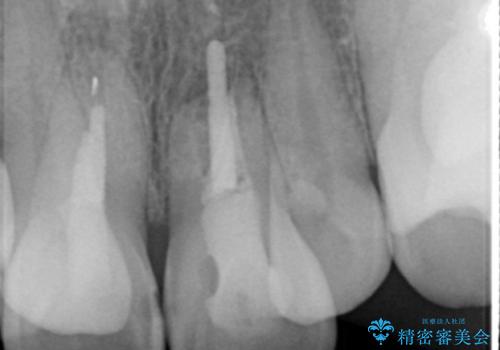

X線写真より、充填剤の突き出た状態の根管治療の再治療を行い、セラミック治療を計画すると同時に、

歯ブラシがしづらく虫歯の原因となっている歯の位置の悪い右上側切歯の抜去を行います。